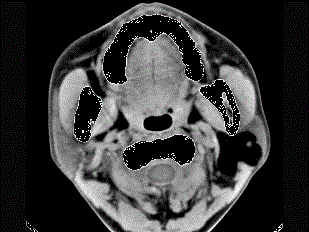

问题 女性50岁,左侧面部肿胀,CT检查如图,应考虑为 ( )

选项 A、左侧腮腺错构瘤 B、左侧腮腺炎 C、左侧腮腺囊肿 D、左侧腮腺脂肪瘤 E、左侧腮腺囊腺瘤

答案 D